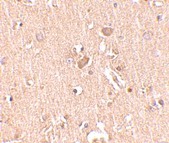

Supportive validation

- Submitted by

- OriGene (provider)

- Main image

- Experimental details

- Immunohistochemistry of MED28 in human brain tissue with MED28 antibody at 2.5 ug/ml.

- Validation comment

- IHC